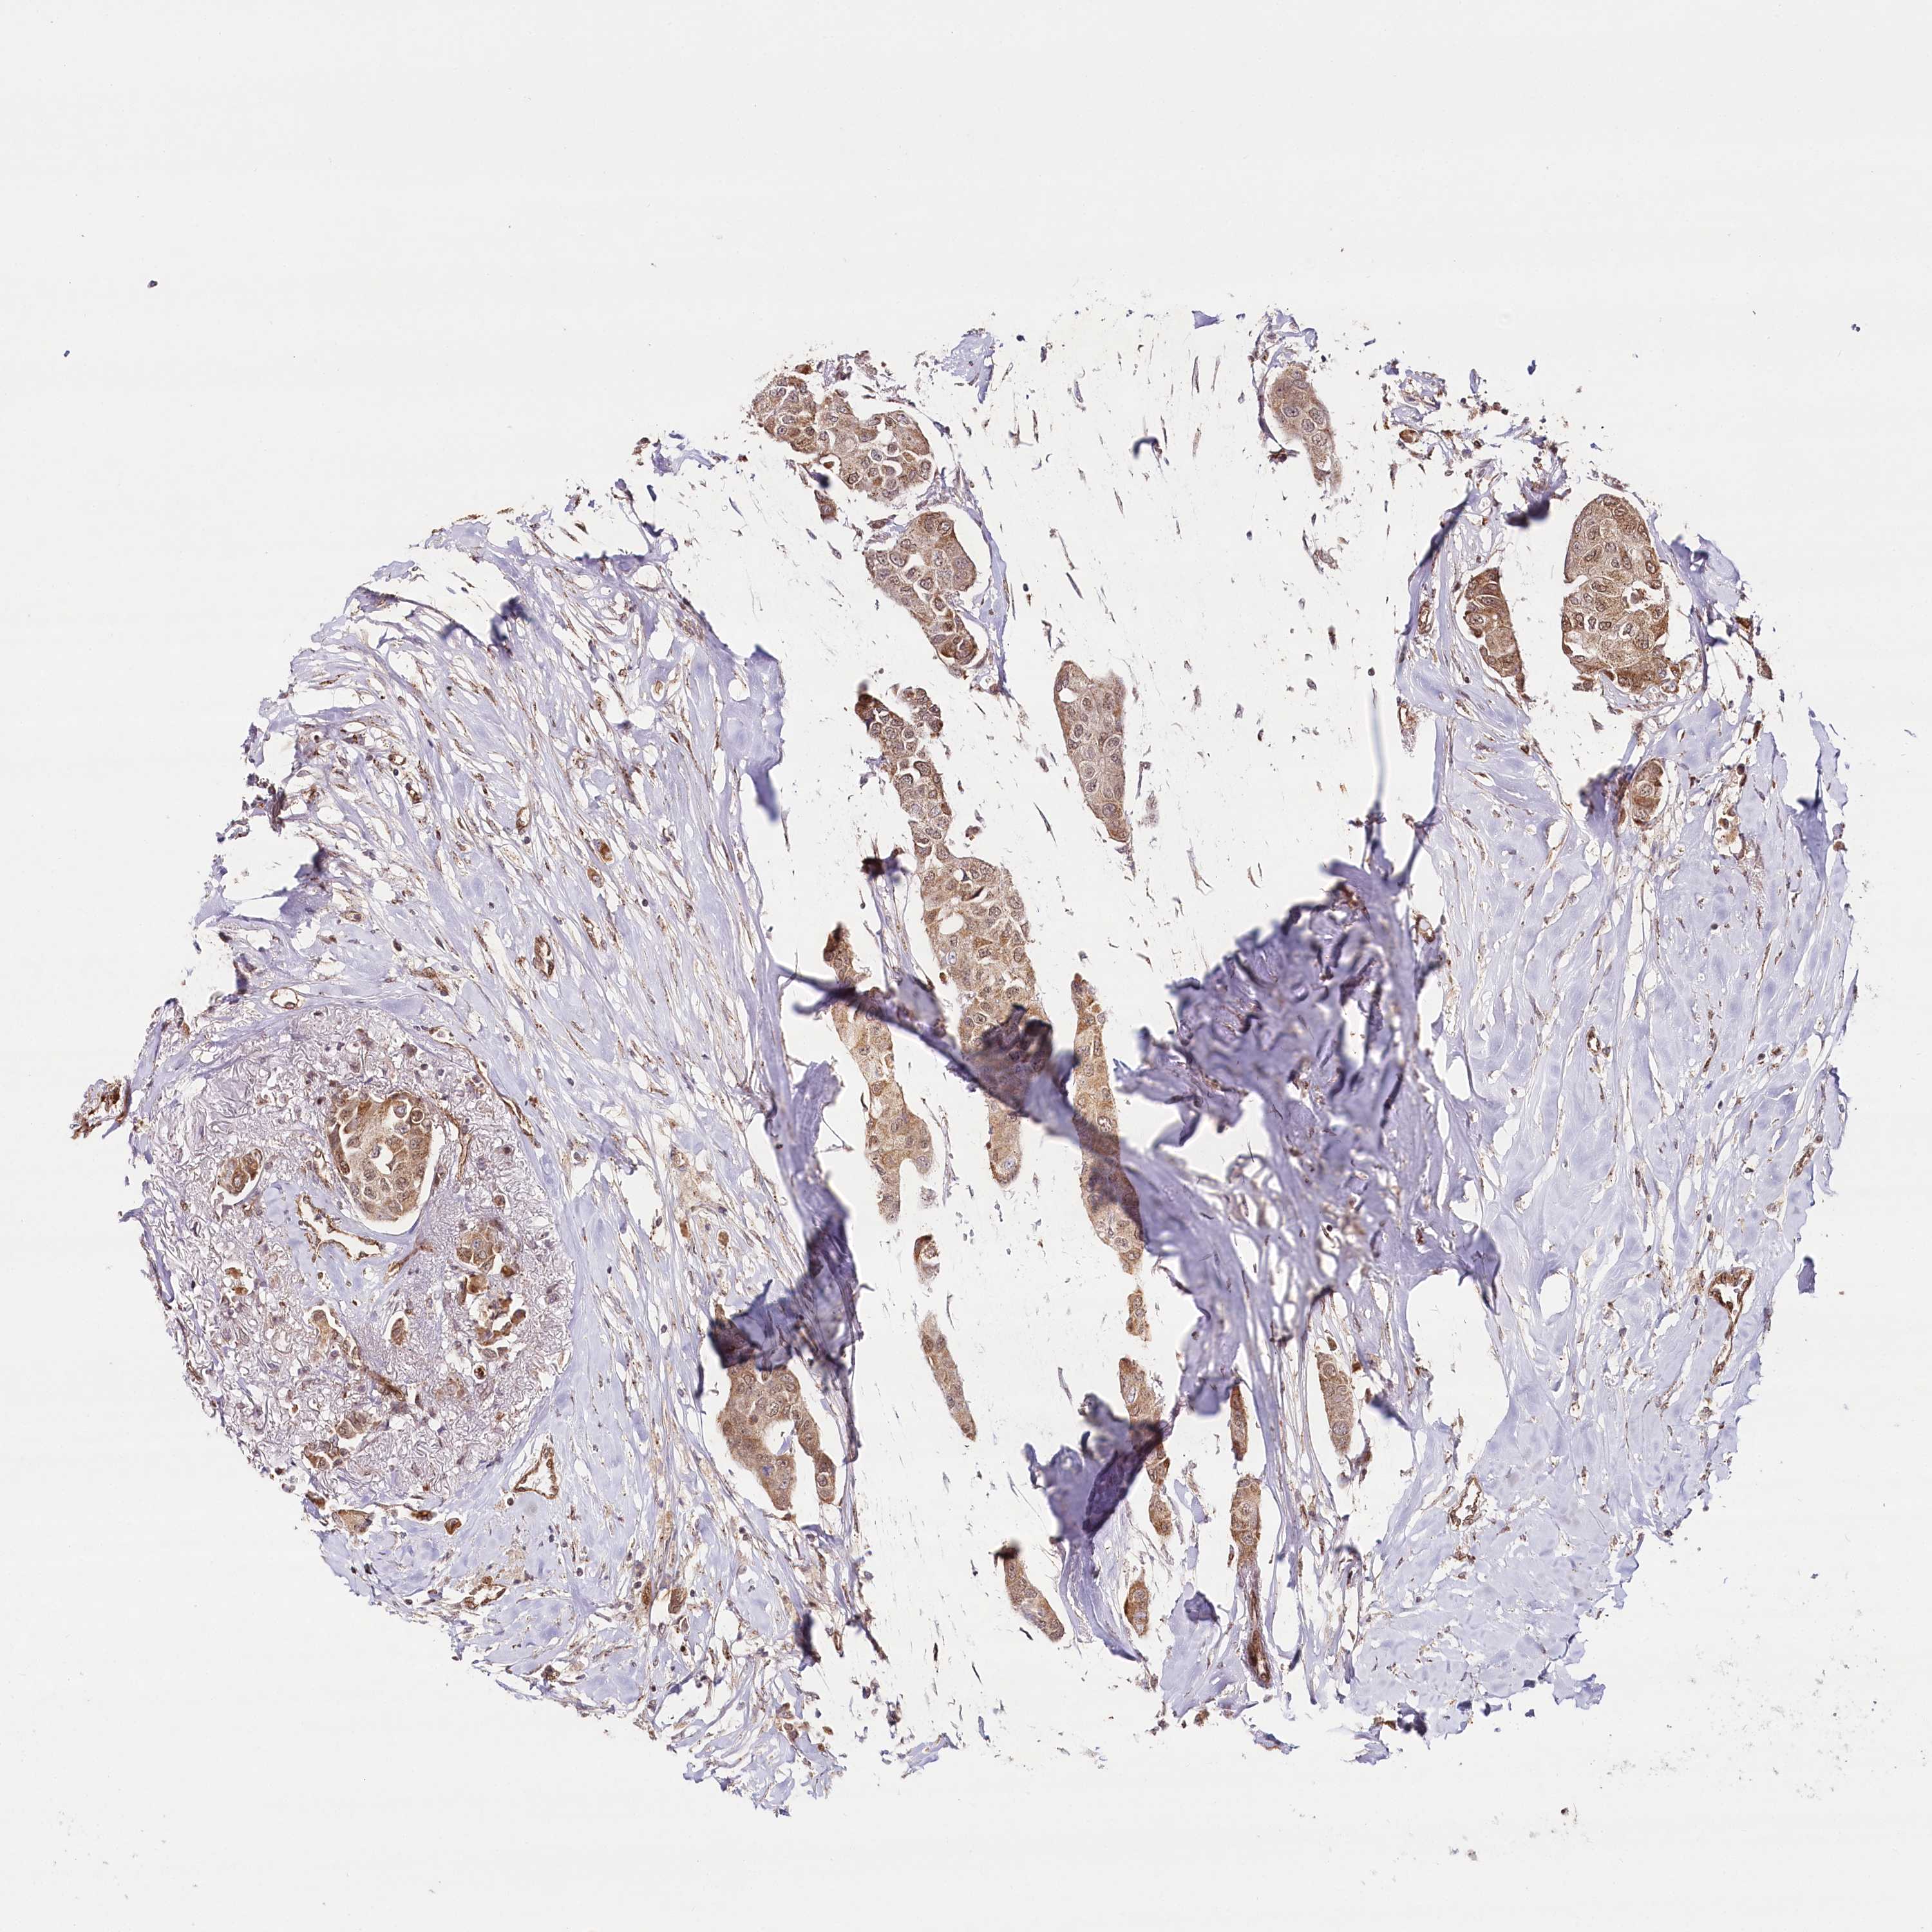

BRCA TCGA BRCA VALIDATION PROTEIN EXPRESSION

ANTIBODIES

AND

VALIDATION